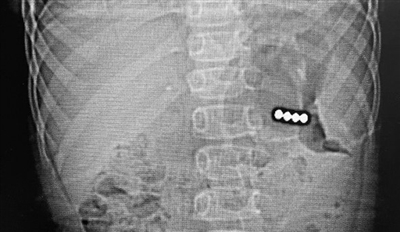

早报2月2日讯 近日,4岁的洋洋(化名)在玩耍时不慎被汽车碰倒,可没想到在当地医院检查时,除了因碰倒造成的皮外伤,竟“意外”发现——洋洋的肚子里有金属样的异物。转诊至青岛妇女儿童医院就医,通过腹部CT、消化内镜探查,救治人员发现磁力珠停留在患儿胃部,已经穿透胃壁,必须尽快手术。

“接诊后,急诊科立即开启异物救治绿色通道,为患儿完善相关检查,并邀请消化内科、小儿普外科专家共同会诊。”青岛妇女儿童医院急诊科工作人员说,经过探查发现有磁力珠停留在患儿胃部,已经穿透胃壁,不尽快取出会造成更严重后果。经过追问患儿也得知,两天前洋洋发现了几粒彩色的磁力珠,以为是糖果就好奇吃了下去。

小儿普外科团队立刻为洋洋进行急症手术,4颗磁力珠全部取出,患儿已康复出院。